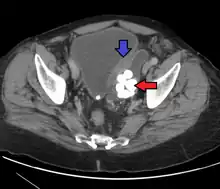

• Bladder diverticula are balloon-like growths on the bladder commonly associated with chronic outflow obstruction, such as benign prostatic hyperplasia in older males. Usually found in pairs on opposite sides of the bladder, bladder diverticula are often surgically removed to prevent infection, rupture, or even cancer.